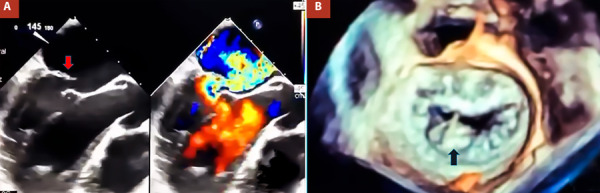

We present the case of a 39-year-old man with a history of progressive dyspnea. Transthoracic and transesophageal echocardiography revealed severe mitral valve (MV) regurgitation due to P2 flail as well as severe tricuspid valve (TV) regurgitation. The patient underwent surgical treatment, including MV repair and TV annuloplasty, performed through a totally endoscopic periareolar approach. Postoperative evolution was satisfactory.